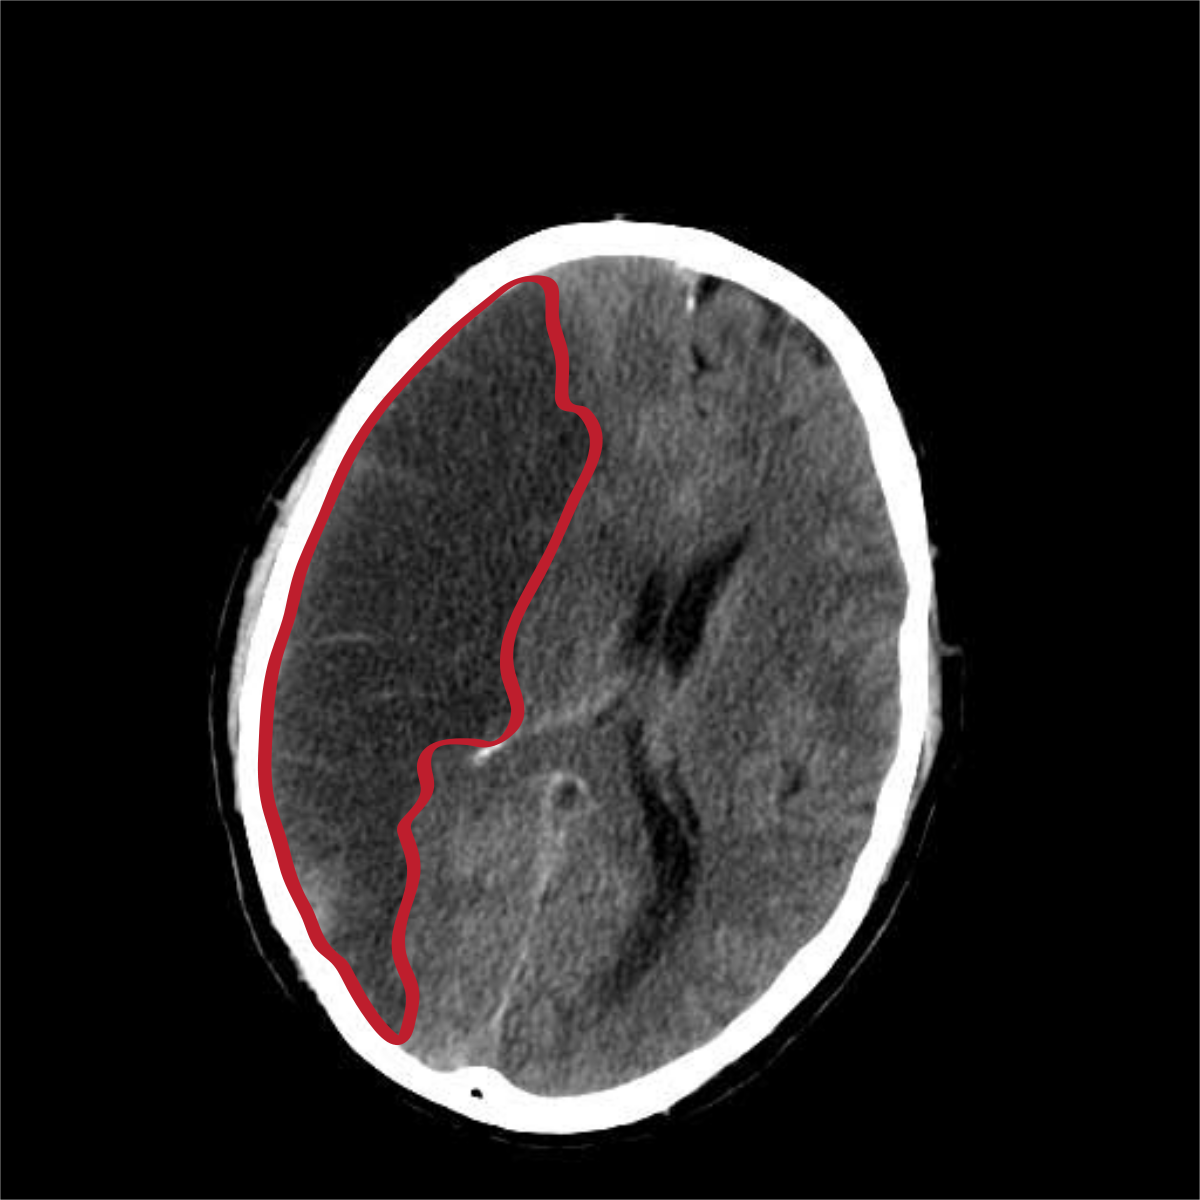

다른 뇌질환들과 달리 주변 시야가 좁아져요. 물체가 여러 개로 겹쳐 보이는 증상들이 아무런 징후도 없이 급격하게 유발돼요. 혈관이 막히면 바로 뇌 손상을 입는 환자가 있답니다. 혈관이 막혔더라도 다른 혈관으로 혈액 순환이 일정 시간 할 수 있는 환자도 있어요. 또한 혈관이 일시적으로 막혔다가 다시 뚫리면서 증세가 완화되거나 없어지는 경우도 있어요.통상 뇌경색 환자 5명 중 1명 꼴로 나타나는 증상입니다. 시력저하는 나이가 들며서 자연스럽게 나타나는 현상이라고 생각하고 쉽게지나치는 경향이 있어요. 시력 저하가 갑자기 발생하면 뇌경색을 의심할 수 있으니, 병원에 방문하시길 권해드리도록 하겠습니다.

허혈성 뇌졸중은 발생 기전에 따라 대혈관 질환에 의한 뇌경색, 심인성 뇌경색 또는 심인성 뇌경색, 소혈관 질환 또는 틈새 뇌경색, 기타 드문 이유가 되는 것에 의한 뇌경색으로 나누어져요. 에피소드는 일정 기간 동안 증상이 완전히 가라앉는 경우입니다.